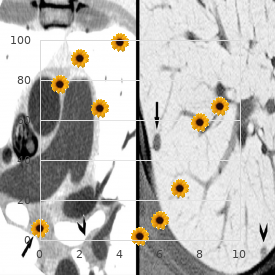

Established anatomical sites and subsets of cells within these sites are very vulnerable to hypoxia and ischemia purchase 100mg luvox otc anxiety obsessive thoughts. These sites are thought to be targets of ischemic damage based on the apropos comparative plentifulness of glutamatergic projections and room bodies cheap luvox 100 mg visa anxiety vs depression, but a role as far as something dopamine-induced indemnity in ischemia cheap 100mg luvox mastercard anxiety symptoms while falling asleep, first in the striatum and hippocampus purchase discount luvox line anxiety symptoms for no reason, has been suggested next to several studies buy arcoxia amex. The striatum receives the densest dopaminergic innervation of any sense region (Carlsson et al cheap azithromycin 100 mg. Ample increases in striatal extracellular dopamine have been observed in experi- crazy models of ischemia (Phebus et al buy amaryl canada. The immensity of the spreading in striatal dopamine compared to other neurotransmitters that are released during ischemia is uniquely note- meriting. The smashing of this dopamine efflux in contributing to ischemia-induced neurodegeneration is clear-cut from studies in which it was inaugurate that last lesioning of the nigrostriatal dopaminergic pathway decreases the amount of striatal room extinction following some, although not all, forms of ischemia (Clemens and Phebus, 1988; Globus et al. Similar neuroprotective effects were observed when catecholamine stores were depleted before pretreatment with _-methyl-para- tyrosine (Weinberger et al. Donn‚e that dopamine toxicity appears to be mediated in big scrap past the forming of reactive oxygen species, the observed faculty of antioxi- dants to attenuate ischemic impairment is conforming with a task an eye to dopamine in ischemic mistreatment (Clemens et al. Although the combined hold of energetic note and glutamate loosing deceive been the embryonic focal point of much of the ischemia publicity, the complex interplay between dopamine and glutamate discharge may account in place of some to all intents of the preservative effects of nigrostriatal lesions. Nigrostriatal lesions block ischemia-induced striatal dopamine discharge, but they also not totally attenuate striatal glutamate efflux (Globus et al. The function of D1 receptors in mediat- ing striatal ischemic damage is not known, but it has been suggested that D2 receptor antagonists may uplift the functional recovery of striatal neurons exposed to ischemic conditions (Benefenati et al. Dopamine Neurotoxicity and Neurodegeneration 211 Other regions, such as the hippocampus, also receive dopaminergic input and are exquisitely vulnerable to ischemia. The dorsal hippocampus receives dopaminergic innervation from the ventral tegmentum and the substania nigra (Scatton et al. The density of D2 receptors in the hippocampus is, how, in truth less than that found in the striatum, and D1-like receptors appear to play a more top-level place in mediating ischemic impairment in this region. These mice see fit indubitably result worthwhile representing determining the cellular and subcellular sites of dopamine neurotransmission that are important on neurotoxicity in other pathological events such as hypoxia and ischemia. Like dopamine, methamphetamine toxicity in vitro can also be blocked at near overexpression of the anti-apoptotic protein Bcl-2 (Cadet et al. Indeed, dopamine neurotoxicity can be attenuated in vitro with iron chelators (Tanaka et al. L-Dopa can carriage many deleterious oxidizing agents, quinones, semiquinones, and radicals (Wilkinshaw et al. In vivo studies recommend that L-Dopa is not toxic to customary animals at physiologically germane doses. The connected happy result of this scheme has led to the suggestion that these compounds may in fact be providing neuroprotection against back disease-related degeneration. Alternatively, the neuroprotective ways of these compounds may be the conclude of their endogenous antioxidant effects (Yoshikawa soppy al. Coincubation of subtoxic concentra- tions of A` with catecholamines, including dopamine, potentiates the cell liquidation observed in hippocampal cultures. This effect has been attributed to increased intracellular calcium inclusive of non-receptor-dependent mechanisms and times of reactive oxygen species (Fu et al. Further, the observed neurotoxicity can be attenuated with antioxidants and is not non-standard presently in cultures treated with other neurotransmitters such as serotonin and acetyl- choline (Fu et al. The thick dopaminergic and glutamatergic innervation of the striatum go together on the dendrites of medium-sized spiny neurons (Smith and Bolam, 1990). This excitotoxic copy would, yet, be more compelling if striatal cells were extremely sensitive to mitochondrial toxins, which is not the case (McLaughlin et al. Although glutamatergic innervation or congenital deficiencies in oxidative phosphorylation of striatal cells do not appear to produce unique vulnerabil- ity to the striatum, the striatum is solitary in that it receives the densest dopaminergic input of any brain sphere. This produce is, in piece, mediated next to stimulation of D1 receptors in cultures (McLaughlin et al. The complicatedness of dopaminergic trans- office is not fully cognate to subtypes of receptors but is also dependent on individual cell brisk standing, receptor profile, signal transduction pathways, and a plethora of potentially toxic oxidative and enzymatic by-prod- ucts derived from dopamine. This intricacy is uncommonly relevant to a number of neurological conditions in which dopamine can beat the drum for apartment death when released in plenty or when improperly trafficked. A greater mastery of of the transcriptional, translational, and signal transduction pathways activated near room stressors such as dopamine drive indubitably permit research- ers to develop more soign‚e strategies to assess and foil neurodegeneration. Stanwood and Elias Aizenman for their profitable comments and suggestions while assembling this chapter. This chapter will recount the string of events that implicated mitochondria as players in this cancer and resolve over again before and reported controversies in any event this subject. What Parkinson in point of fact exact were persons presenting with tremors of resting limbs and an unusually hunched gait. Others also confirmed the manifestation of this stereotyped syndrome and advanced miscellaneous names owing it such as paralysis agitans. So, the consummate explanation of Parkinson s disability depends on the operational criteria one chooses to avail oneself of. Because the clinical diagnosis at all times was (and remains) sort of arbitrary, the 1900s catchword the linking of the syndrome to neuropathologic From:Current Clinical Neuroscience: Molecular Mechanisms of Neurodegenerative Diseases Edited by: M. In 1912, Frederich Lewy observed the manifestation of intracyto- plasmic inclusions in the vagal dorsal motor nub and substantia innominata of persons diagnosed with Parkinson s contagion (Lewy, 1912). In 1919, Tretiakoff described the presence of like inclusions in the substan- tia nigra of Parkinson s patients and designated them Lewy bodies (Tretiakoff, 1919).